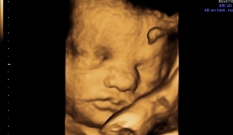

O feto está cada vez mais parecido com um bebê: a pele está menos enrugada devido ao acúmulo de gordura e muitos já têm “bochechas”.

| No ultrassom do terceiro trimestre, quantifica-se o líquido amniótico do feto, revisa-se a sua morfologia e seu peso é estimado por medidas da cabeça, do abdômen e do fêmur. |